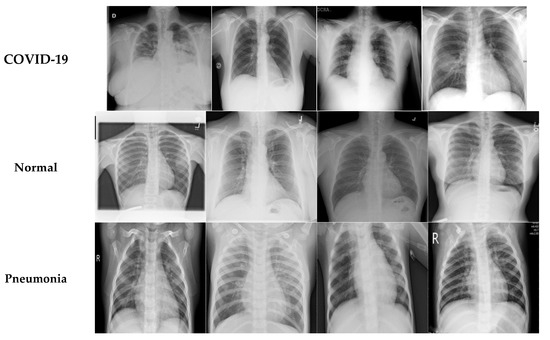

In this study, two different open-access sources were used as our basic experimental datasets. The CT scan dataset [34] had a total number of 2481 CT images divided into 1229 normal cases and 1252 COVID-19 patients, whereas the chest X-ray dataset [35] had 6939 sample images consisting of three classes (COVID-19, normal, and pneumonia), with 2313 samples used for each category. Figure 6 shows samples from the CT scan dataset and Figure 7 shows samples from the chest X-ray dataset. Next, the database was split into training and testing sets. The details for the training and testing samples are shown in Table 1 and Table 2 for the CT scan and chest X-ray datasets, respectively, with the results of the different models displayed in the subsequent tables. Table 1 describes the splitting strategy used for the training and testing sets in the experiment for the CT scan dataset. The 80–20 training–testing ratio was adopted in our experiments. The COVID-19 class had 1013 images for training and 239 images for testing, while the normal class had 971 images for training and 258 for the testing set. Table 2 describes the splitting strategy used for the chest X-ray dataset. This dataset had an equal distribution, with 1850 images for training and 463 images for testing in each class. Data augmentation techniques were employed here to effectively increase the number of training samples. The images were augmented through cropping, noising, brightness modifications, contrast modifications, and random flipping.

Figure 7.

Sample COVID-19, normal, and pneumonia images.